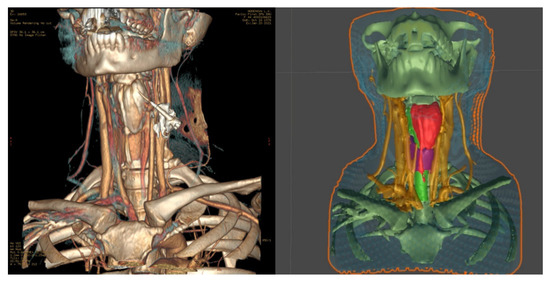

- We transformed the CT into a 3D model using a segmentation approach with respect to the set density threshold or the area of interest in the 3D Slicer. This allowed us to isolate all key anatomical structures of the neck as a series of separate three-dimensional models. After that, resulting 3D models were optimized and cleaned up using the procedural toolkit in Houdini (up to 75–95% polygon reduction); we then transformed the MSCT into a 3D model using a segmentation approach with respect to the set density threshold or the area of interest. This allowed us to isolate all key anatomical structures of the neck separately as a series of three-dimensional models;

- We visualized 3D models using mixed reality smartglasses and the developed software, which has preset parameters for referencing the markers to the three-dimensional model. It has an integrated basic interface [20], which allows the user to display the required anatomical elements as well as customize the parameters of the marker tracking system;